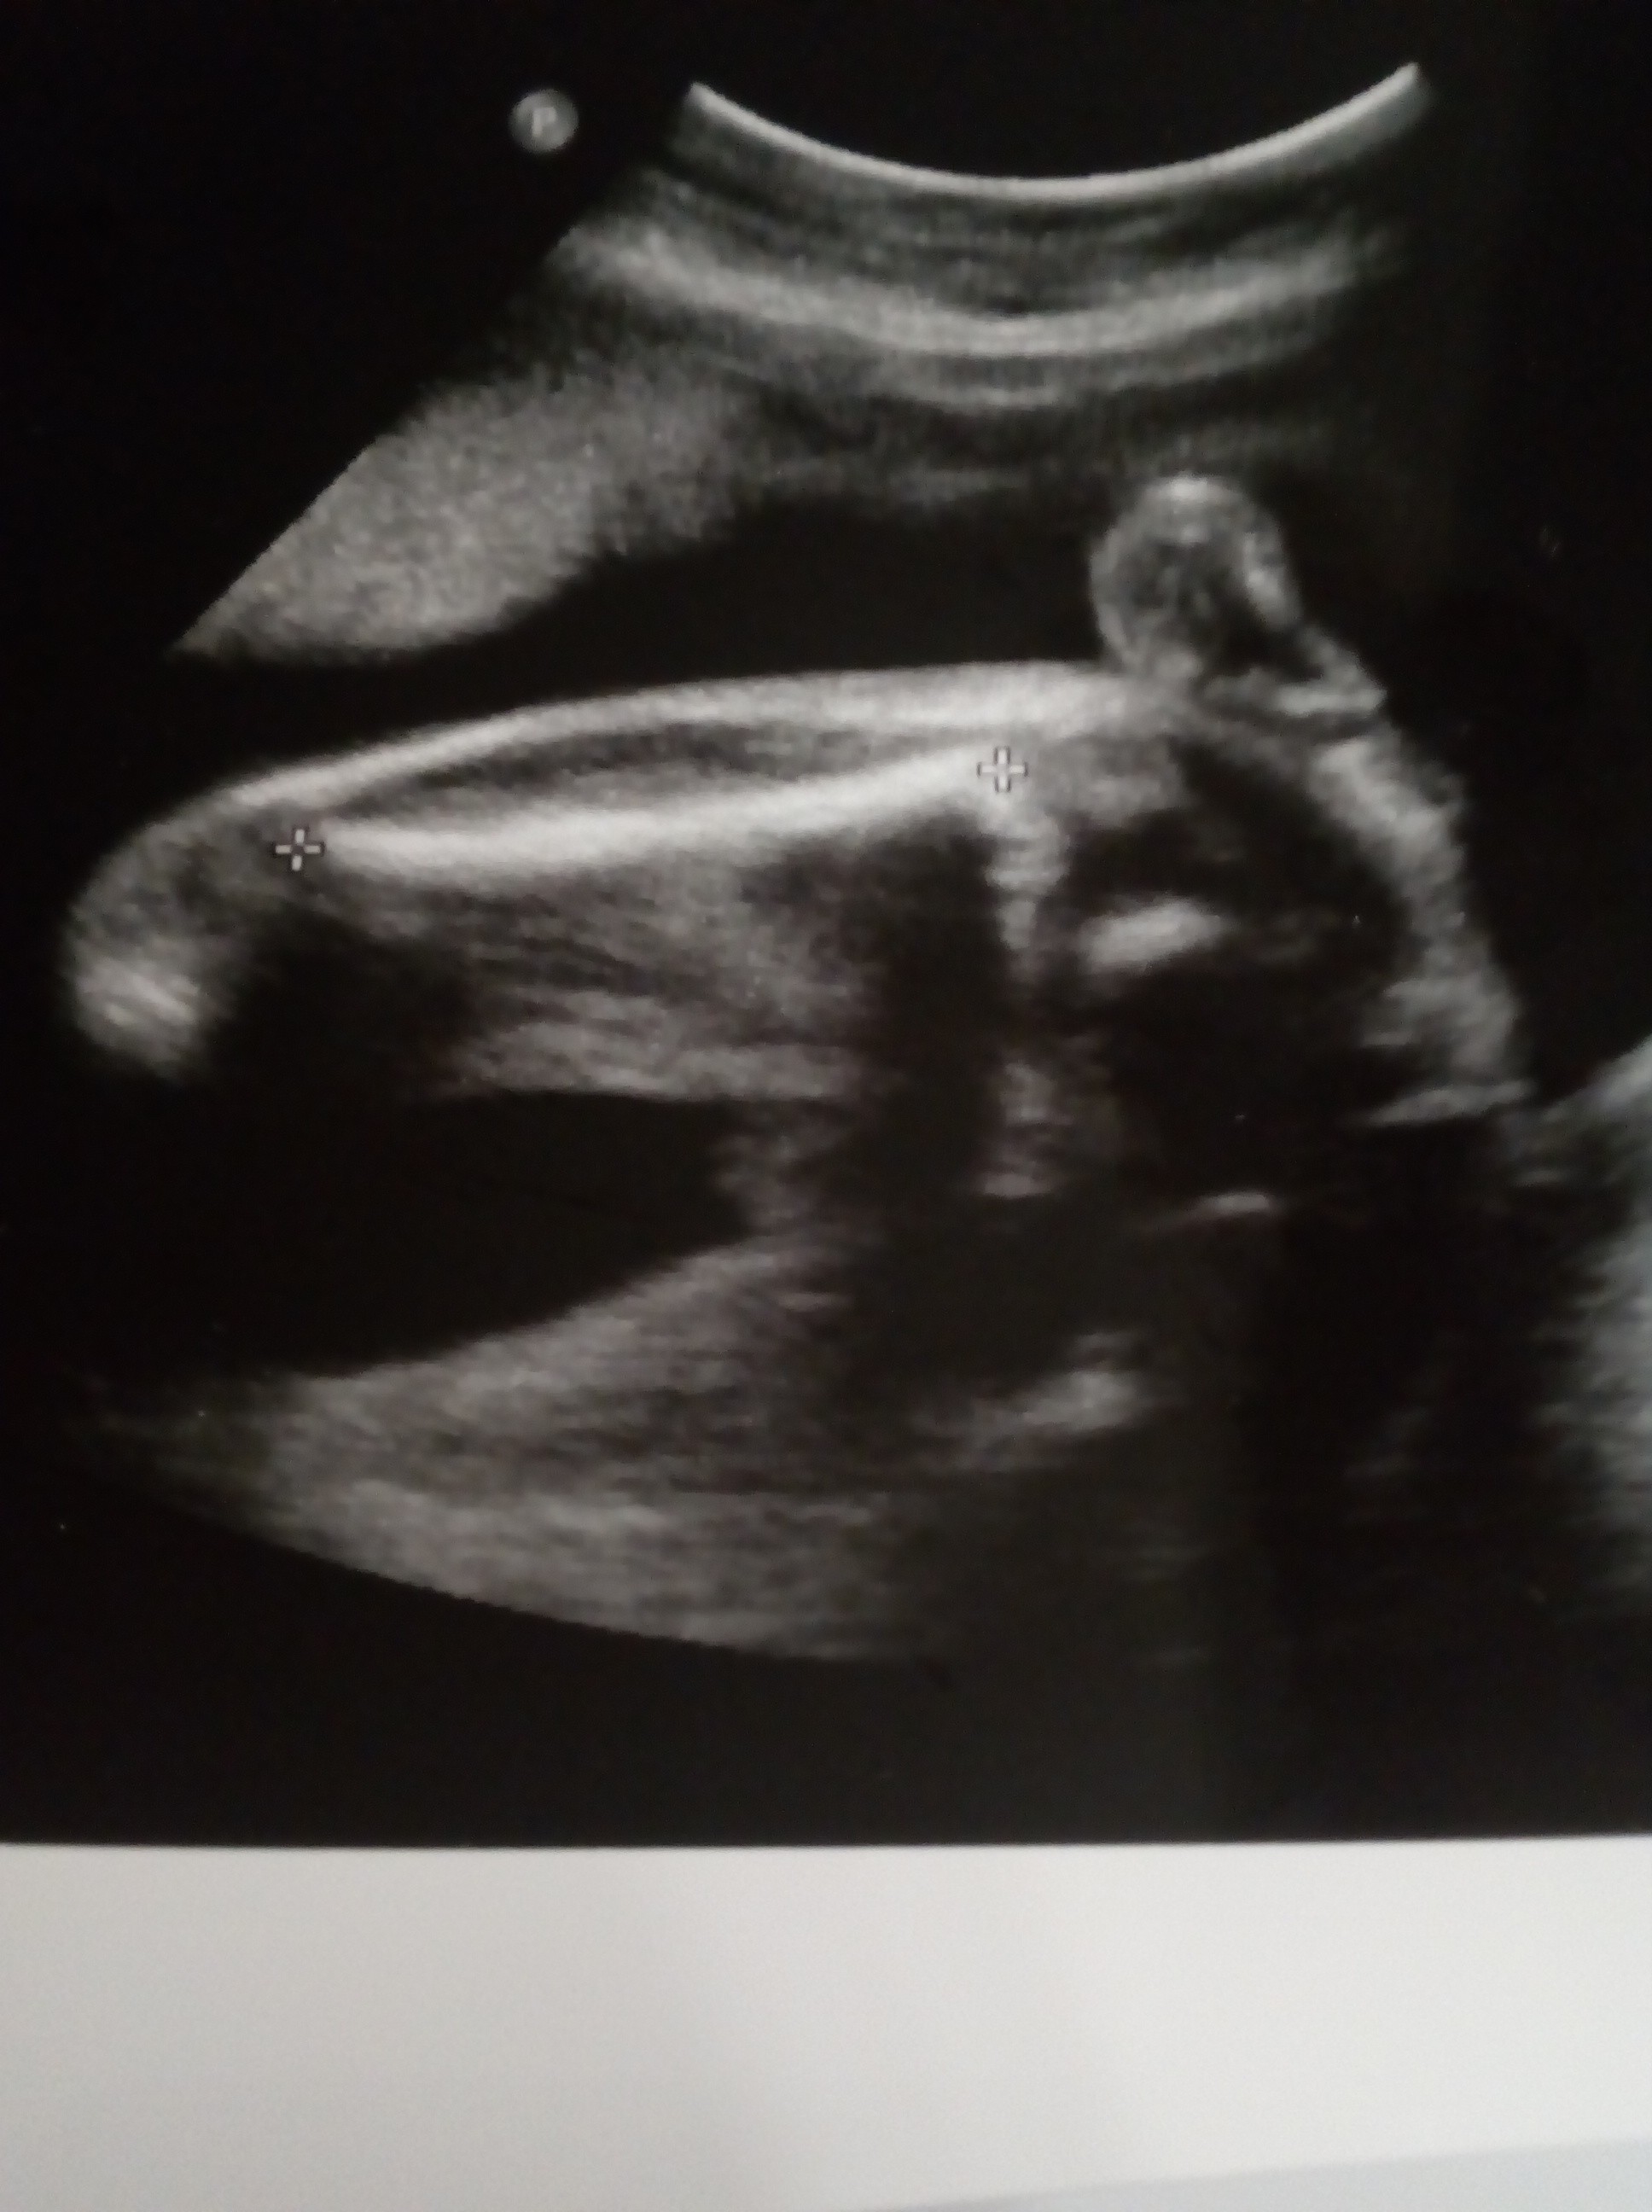

Katrinaa dla mnie to raczej chłopczyk jeśli to 24 tc prawie. Widać pęcherz i dość daleko jest to „coś”. Ale tez nóżki troszkę złączone wiec ciężko tak z samego zdj. Masz jakieś inne? Lekarz podczas usg pewnie więcej widział. Wcześniej nie określał płci?

Dzieki dziewczyny za opinie Lekarz zasugierowal dziewczynkę, chodz za bardzo nie był pewnien...

Imama niestety nie mam wiecej zdjeć z tego usg, a w 12 tyg lekarz dawal 50/50%...